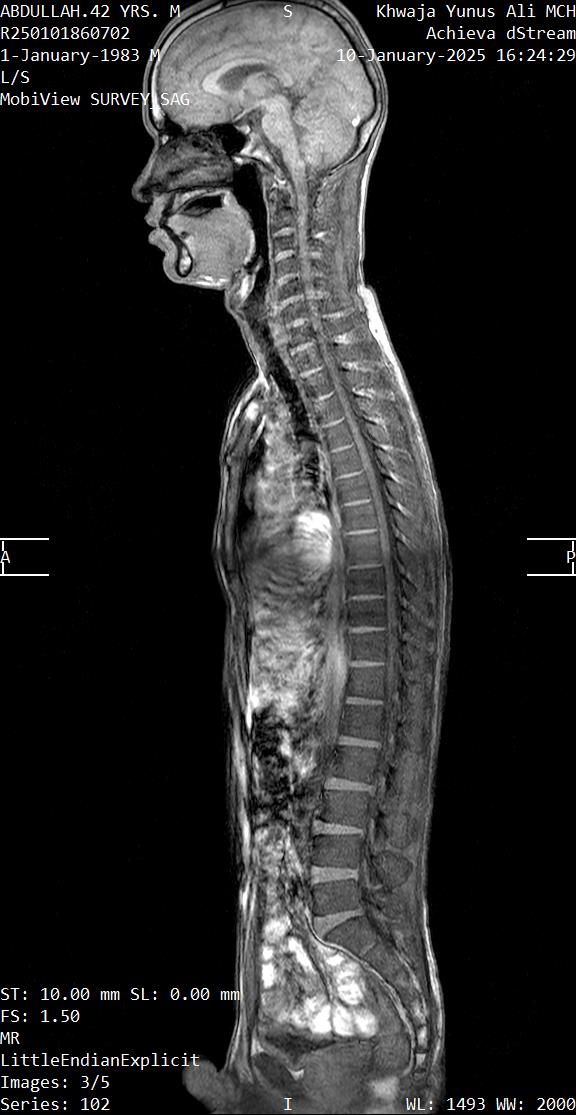

- ইমেজিং: X-Ray (হাড়ের পরিবর্তন), আলট্রাসনোগ্রাফি (USG) বা MRI (নরম টিস্যু/কার্টিলেজের বিশদ)।

আমি চিন্তা করলাম — এটি Phrenic Nerve সমস্যার কারণে হতে পারে।

Phrenic Nerve কী?

Phrenic nerve হলো আমাদের Diaphragm (শ্বাস নেওয়ার প্রধান পেশী)-এর মোটর ও সেন্সরি নার্ভ। এটি স্পাইনকর্ডের C3 থেকে C5 ভার্টিব্রা থেকে উৎপন্ন হয়ে ঘাড় ও বুকের খাচা হয়ে ডায়াফ্রামে পৌঁছে।

এই নার্ভের ক্ষতি হলে ডায়াফ্রামের কার্যক্ষমতা হ্রাস পায়, এমনকি সম্পূর্ণ বন্ধও হয়ে যেতে পারে।

যেহেতু রোগীর ইতিহাসে ঘাড়ে আঘাত ছিল এবং সমস্যা ঐ অঞ্চলেই, সেহেতু Phrenic Nerve Injury হওয়ার সম্ভাবনাই বেশি। তার লক্ষণও এর সাথে মিলে যায়।